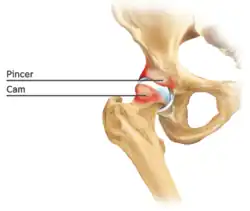

Figure 6. Diagram of the bony pathology of both cam and pincer impingement

Femoroacetabular impingement (see fig. 6)

Cam impingement is created by the abnormal development of the femoral head-neck junction causing what has previously been described as a 'pistol-grip deformity'. This type of deformity is characterised by varying amounts of abnormal bone on the anterior and superior femoral neck at the head-neck junction (see fig. 6). The head-neck junction is at the base of the ball of the hip, where it joins the short neck, which in turn carries on downwards into the femur, or thighbone, itself. A bony protrusion or bump at the head-neck junction has been likened to a cam, an eccentric part of a rotating device. This leads to joint damage as a result of the non-spherical femoral head being forced into the acetabulum mainly with flexion and/or internal rotation. This may impart compression and shear forces to the articular cartilage, and may lead to labral tears and peeling away of the articular cartilage from the underlying bone, so-called cartilage delamination (see fig. 8).[9][10]